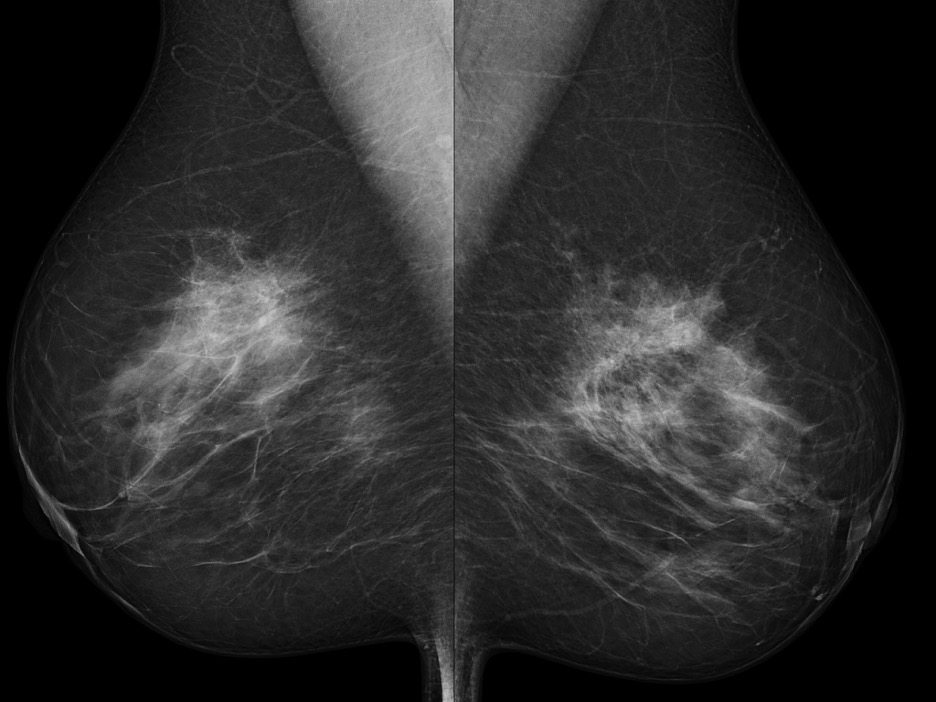

- Found on routine mammography

- Architectural distortion with irregular borders and microcalcifications

- Mammography often shows low-intensity, spiculated masses that are indistinguishable from spiculated carcinomas

- Mammogram shows dense pattern